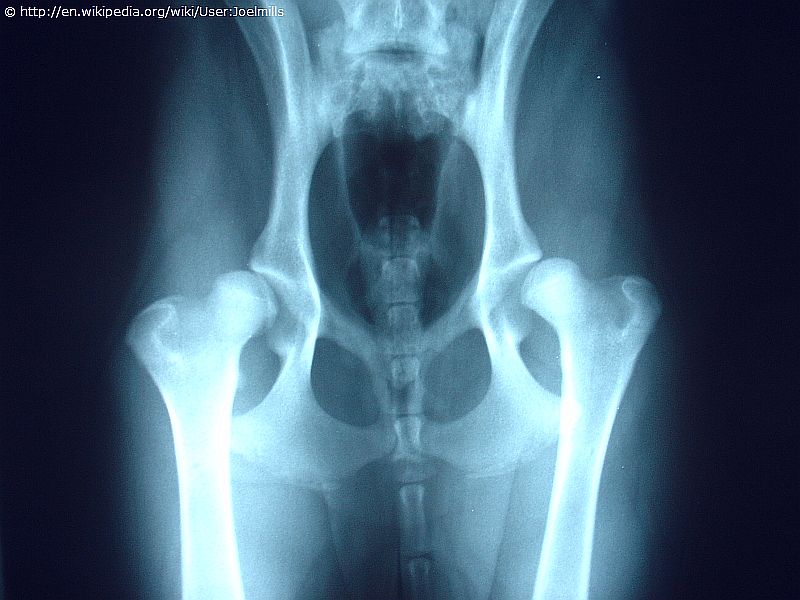

Röntgenbeispiele: Hüftgelenke im Vergleich 🩻

Hinweis: Die meisten positiven Befunde beim Australian Shepherd bleiben glücklicherweise mild (C) und oft lebenslang symptomfrei. Schwere Formen (D/E), wie im rechten Beispiel gezeigt, sind bei verantwortungsvoller Zucht sehr selten.

Das korrekte röntgen kann nur in Narkose erfolgen, da für aussagekräftige Bilder die Hinterbeine eingedreht und die Gelenke überstreckt werden. Nur das richtige Lagern des Hundes führt anschließend zu auswertbaren Bildern. Da HD auch umweltabhängig ist, ist gute Aufzucht – zuerst beim Züchter und später beim Besitzer – wichtig, um das Risiko zu minimieren.